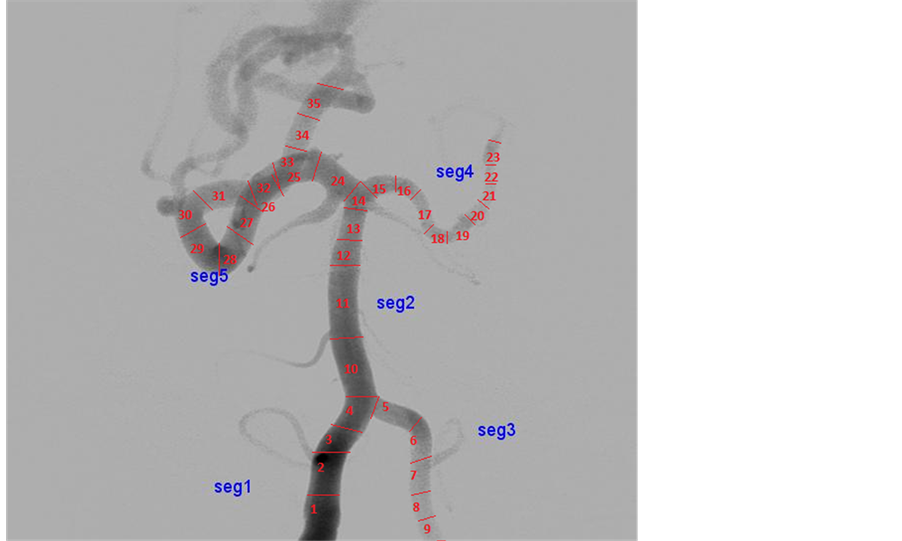

This section describes method for segmenting the Digital Subtraction Angiogram (DSA) images. The data is obtained from KMC Manipal. The input image is preprocessed using Gaussian noise and Hessian matrix based filtering is applied to angiogram images, to detect the tubular structures of vessels using eigenvalues [5] . Figure 2 shows adaptive segmentation technique methodology. The preprocessed image is segmented using OTSU segmentation to create an initial vessel segment as shown in Figure 3. The length and diameter of vessel is calculated using the ROI tools on the vessel segment [6] [7] . The diameter of the initial part of segmented region set as reference node-P1. The diameter is calculated for every small change of the vessel. The sub segment of vessel is created, whenever there is an increase of 10% of diameter of newer segment more than reference diameter, which is shown as segment-P2 as shown in Figure 4. The entire vessel is segmented into smaller sub- structures for variation in diameter with comparison to reference diameter. This is repeated for entire vessel structure. This leads to different combinations of sub-segments of vessels.

Figure 4. Vessel diameter measurement. Source: KMC manipal [10] .

The adaptive segmentation of threshold based adaptive segmentation for CAVM patients is implemented using MATLAB. Figure 5 shows various segment sub-division based on the threshold factor. The adaptive segmentation using 5% produces more sub-segment and with more accurate in hemodynamics measurements. Twenty-three CAVM patients with 150 different vessel location of DSA datasets were studied as part of the adaptive modeling and 30 simulated data are created with equivalent complexity of DSA, has been evaluated for more than 150 vessels locations for sub-segmentation of vessels.

Figure 5. Adaptive threshold―10 and 5 percentage vessels segments. Source: KMC Manipal.